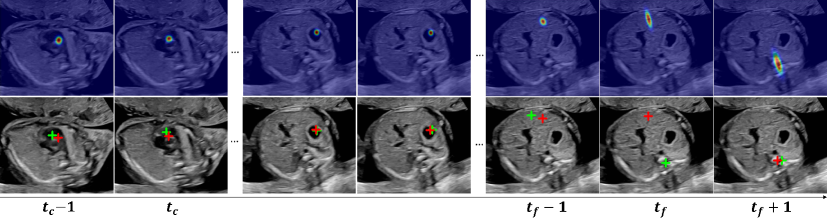

Refer to caption

Figure 5: Visualization of predicted saliency map (top row), gaze point (bottom row, red star), and corresponding ground truth gaze point (green star) for an ACP searching sequence. tcsubscript𝑡𝑐t_{c} and tfsubscript𝑡𝑓t_{f} are timestamps for coarse and fine adjustment, respectively.

Figure 5 shows an example of predicted visual saliency and gaze point deduced from the generated gaze shift distribution. The predictions are highly accurate in all timestamps except for a significant gaze shift at frame tfsubscript𝑡𝑓t_{f}. However, the predicted saliency map at tfsubscript𝑡𝑓t_{f} correctly estimates the orientation of gaze shift. Saliency map-based numerical metrics are also evaluated in the supplementary material, where the multitask model generally outperforms the single-task one. In general, modeling the gaze information as a bi-variate distribution is technically advantageous over a saliency map-based predictor, as the problem complexity is reduced from optimizing a large feature map to only a few parameters for probability density estimation. The flexibility in gaze sampling also preserves the variety in gaze movements.